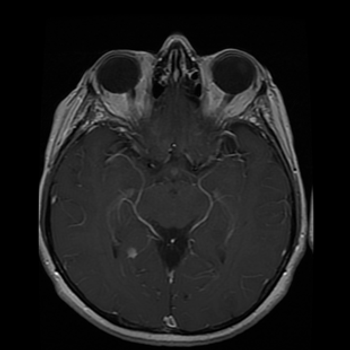

Emerging technology gives radiologists an unprecedented view of the brain.